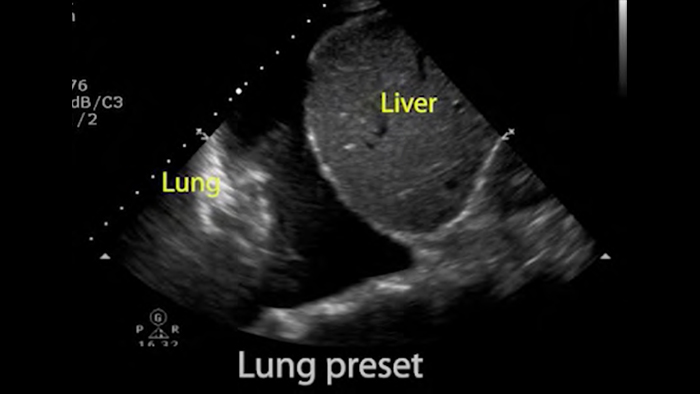

Utilizaţi Lumify pentru evaluarea căilor respiratorii şi pulmonare

Soluţiile Lumify POCUS vă pot ajuta să detectaţi tubul endotraheal, să asistaţi procedurile urgente de cricotiroidotomie, să diagnosticaţi efuziunea pleurală şi bolile alveolare interstiţiale.

Bazele ecografiei pulmonare